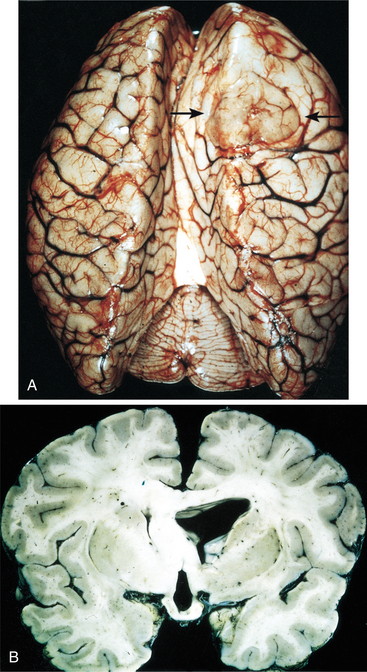

Pathogenesis.: Low-grade astrocytomas include grades I and II. Grade I includes pilocytic astrocytoma (composed of fiber-shaped cells), sometimes termed juvenile astrocytoma, and is considered benign by some and malignant by others.73,133 Grade I astrocytoma grows slowly and often becomes cystic. It is composed of astrocytes with densely staining nuclei and scanty cytoplasm and is usually relatively acellular. The cells are uniform and closely resemble mature resting or reactive nonanaplastic astrocytes (well differentiated). Mitoses are absent or very rare.59,73 Although these are slow-growing tumors, they may become large.4 See Fig. 30-4 for a photograph of a well-differentiated astrocytoma. Grade II astrocytomas may be diffuse, infiltrative, and/or fibrillary, and have more anaplastic features. Fibrillary refers to the neuroglial fibrils. Other types are protoplasmic (cells that consist largely of protoplasm) and gemistocytic (large, densely packed cells with a globoid appearance).133 There is moderate cell density. Fig. 30-5 shows the appearance of computed tomographic (CT) and MRI astrocytoma scans with and without the use of contrast. The contrast agent, such as gadolinium, distinguishes the edema from the actual tumor. The larger the extent of the edema after administration of an intravenous contrast agent, the more malignant the lesion is likely to be.83 Cerebral astrocytoma presents as a solid, grey mass with indistinct boundaries. Differentiation falls somewhere within a spectrum from well-differentiated (grade I) tumors to more anaplastic (grade II) tumors.45 Astrocytomas in the cerebellum are often cystic and well circumscribed.

Figure 30-4 Well-differentiated astrocytoma. A, The right frontal tumor has expanded gyri, which led to flattening (arrows). B, Expanded white matter of the left cerebral hemisphere and thickened corpus callosum and fornices. (From Kumar V, Abbas, AK, Fausto N, eds: Robbins and Cotran pathologic basis of disease, ed 7, Philadelphia, 2005, Saunders.)